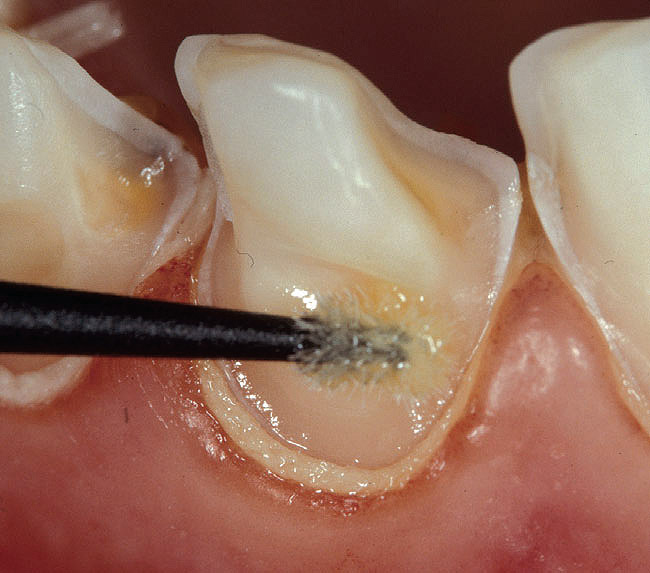

Figure 2h  The priming agent (hydrophilic  monomer) is applied to the dentin with a  gentle brushing motion for at least 20 seconds.  Several applications of fresh primer  are recommended.

Figure 2h

Figure 2i  The priming agent (hydrophilic  monomer) is applied to the dentin with a  gentle brushing motion for at least 20 seconds.  Several applications of fresh primer  are recommended.

Figure 2i

Figure 2j  The dentin surface is  suctioned again to eliminate the solvent from  the priming solution.

Figure 2j